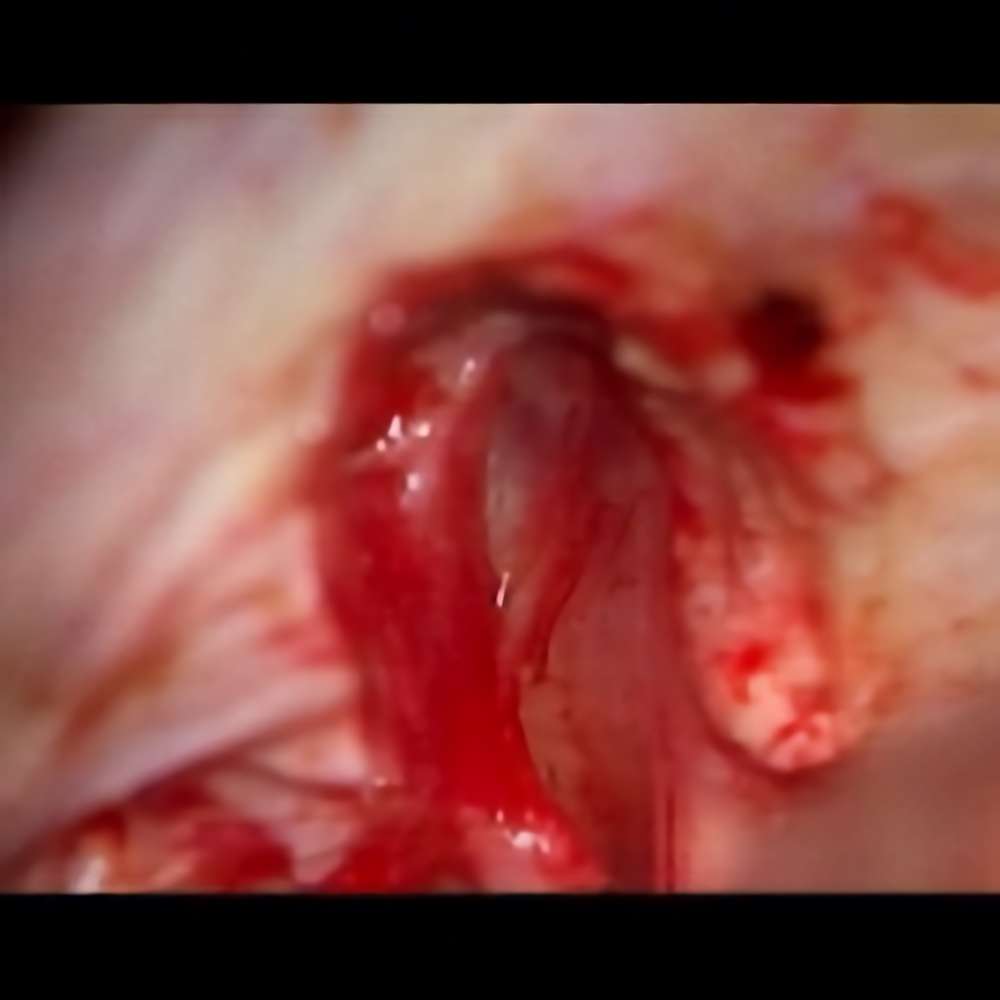

術中写真

摘出 中